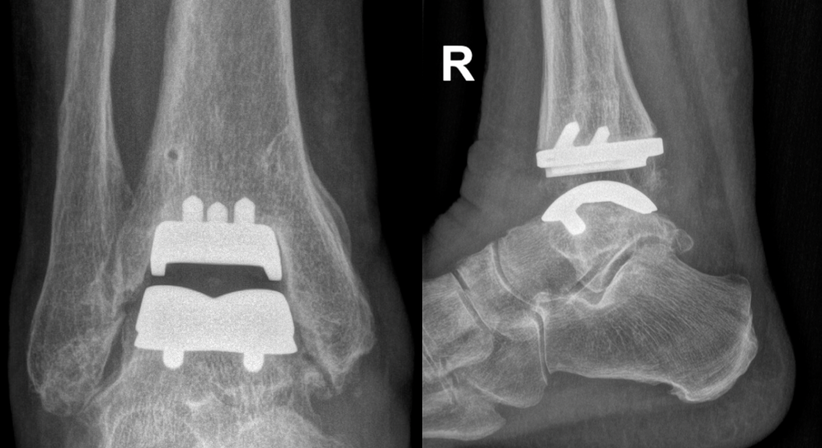

Endoprothesen:

Der künstliche Gelenkersatz hilft bei schwerer Arthrose, Schmerzen zu lindern und Beweglichkeit zu erhalten. Hierzu verwende ich PSI (Patienten-spezifische Implantate), bei der die Schnittblöcke für die Prothese mittels Computertomographie individuell für Sie angefertigt werden.